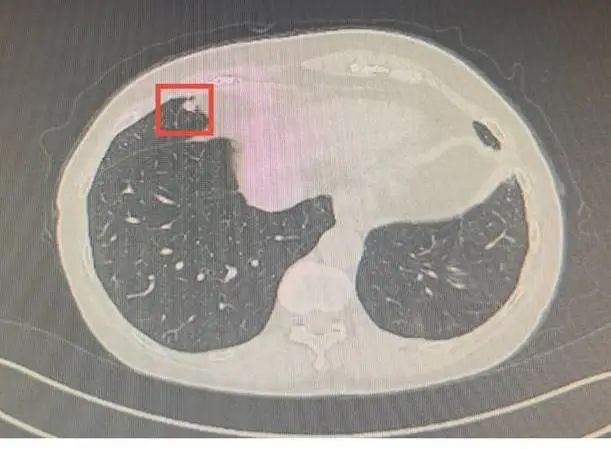

72岁的刘依姆五年前曾因左下肺腺癌在省立医院接受手术。然而,前些日例行体检复查中,右肺又被查出一个9mm×8mm的实性结节。影像科医生依据结节的形态特征,考虑有可能是“炎性病变”,给随访观察或抗感染治疗后复查的建议。

(右肺再查出结节)

刘依姆和家人却十分不放心。怎么肺部又会长出结节?这个结节和之前的肺腺癌有关系吗?家人陪着刘依姆再次来到省立医院胸部医学中心,临床医生结合刘依姆的病史,怀疑这个结节很有可能又是肿瘤。

面对影像科与临床团队的意见分歧,胸部医学中心迅速启动多学科会诊(MDT)机制,经团队详细复习病史及历年影像资料,术前考虑原发性肺癌,且已为实性改变,建议尽快进行外科微创手术,术中送检病理证实确为肺癌。由于手术及时,术后刘依姆恢复良好,无需进一步放化疗,提高了生活质量及预后。